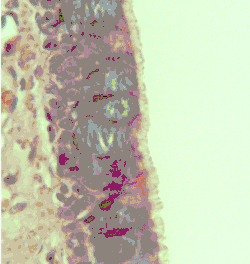

Illustration depicting the respiratory epithelium. Basal cells labelled as stem cells.